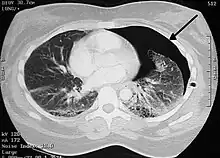

Le scanner thoracique permet de faire le bilan des blebs et des bulles des 2 poumons, de dépister une éventuelle tumeur pulmonaire et de connaître l’état du poumon sous-jacent.